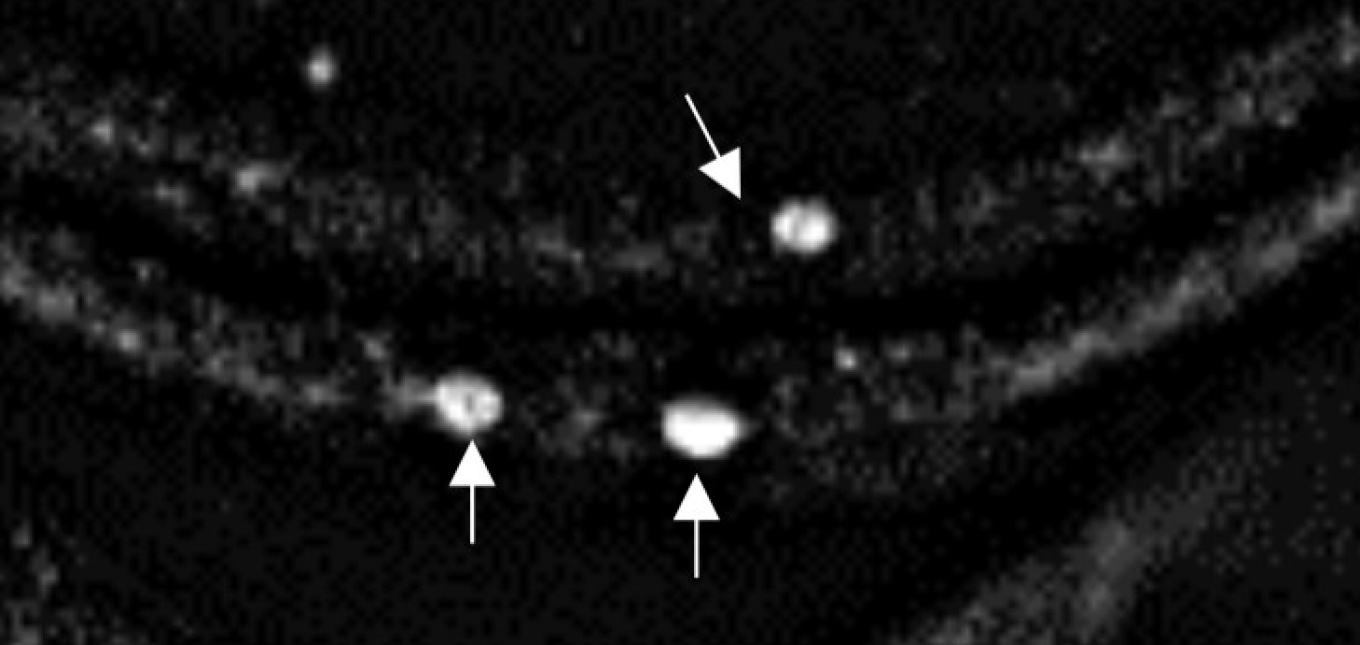

An epifluorescence microscope image shows clumps of human alpha-synuclein aggregating in the neurons of a fruit fly larva. Credit: Anderson, Hirpa, Zheng, Banerjee and Gunawardena, Frontiers in Cellular Neuroscience, Jan. 2020. The image is cropped from a graphic published in the journal article, which is distributed under Creative Commons Attribution License CC BY 4.0 (https://creativecommons.org/licenses/by/4.0/).

Alpha-synuclein is known to form abnormal clumps in the brains of patients with Parkinson’s, but scientists are still trying to understand how and why this happens.

The new study explores alpha-synuclein’s basic properties, with a focus on a section of the protein known as the non-amyloidal component (NAC). The research was done on fruit fly larvae that were genetically engineered to produce both normal and mutated forms of human alpha-synuclein.

“We show that in fruit fly larvae, we’re able to prevent some problems mimicking symptoms of Parkinson’s disease, such as accumulation of alpha-synuclein in neurons,” says Gunawardena, PhD, associate professor of biological sciences in the UB College of Arts and Sciences.